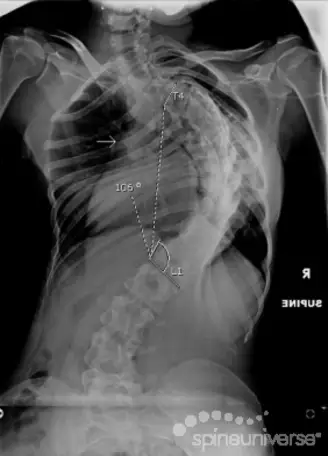

بعض الحالات زاوية الانحناء فيها 20 درجة، وأخرى قد تصل إلى 40 درجة أو أكثر.

يبدأ الطبيب بمراجعة صور الأشعة السينية لتحديد زاوية واتجاه الاعوجاج. كما يجري فحصًا سريريًا لملاحظة وقفة الطفل، شكل الكتفين، واستقامة الحوض.أخذ المقاسات الدقيقة

لا يتم اختيار الحزام بناءً على مقاس عام مثل صغير أو متوسط، بل يتم الاعتماد على أجهزة متطورة مثل الماسح ثلاثي الأبعاد. الهدف أن يكون الحزام مطابقًا لشكل جسم الطفل بالملليمتر.